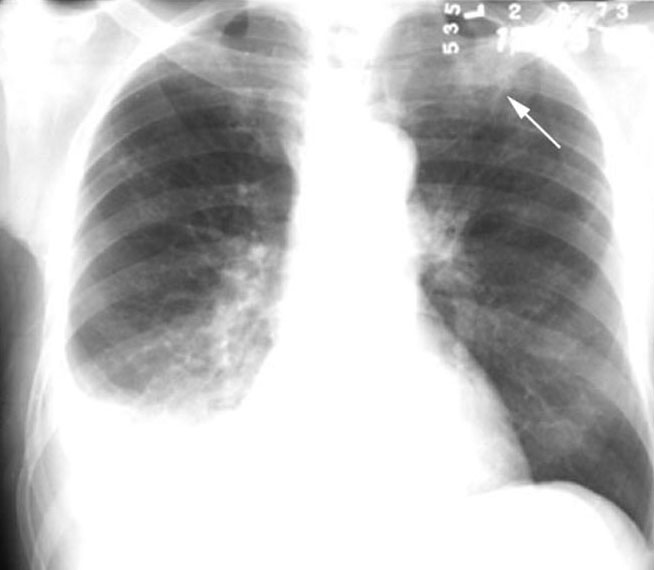

Tuberculosis

LUL cavity

• Cavity behind clavicle - note increased density of clavicle in the region over lying cavity

Pleural effusion on right